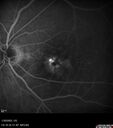

83 year old man Retired aerospace engineer. Blurred vision in both eyes with complex eye history. No acute changes noted by patient. Prior macula-on retinal detachment repair in the right eye a year ago (buckle, vitrectomy, laser, gas, ST Kenalog). Medical Hx: Hypertension, Systemic. Hyperlipidemia. Asthma. Surgical Hx: left shoulder ac separation 2013. Turp 2010. Systemic Meds: Lisinopril, 10 mg oral tablet bid. simvastatin QD. muscinex DM QD. Metformin 100 MG QD. Allergy Medicine. HCTZ QD. PRILOSEC QD. MYBETRIC. MONTULAKAST. Aspirin 81 mg. QUETISPINE 150 MG QD. ESATATOPRAM 20 MG QD. VA OD: Dcc20/50 VA OS: Dcc20/50-2 IOP: TP: OD:15 OS:16 Converted to wet AMD after a single Izervay Treatment

Conversion to Wet AMD after Izervay27 views83 year old man whose left eye had minimal GA and converted from dry to wet AMD after a single Izervay treatment00000